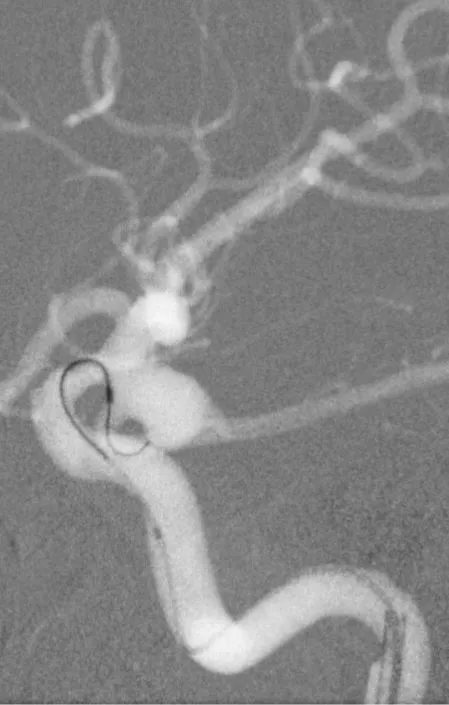

造影显示左侧后交通动脉瘤

椎动脉造影没发现大脑后动脉,双侧的大脑后动脉都是由颈内动脉-后交通动脉发出,双侧胚胎型大脑后动脉

我们来看看动脉瘤的结构:红色为颈内动脉走向,绿色为后交通动脉走向,蓝色为动脉瘤

栓塞的要点,既要致密填塞,又要保证颈内动脉和后交通动脉的通畅。决定通过对侧前交通动脉-颈内动脉远端-后交通动脉途径来置入输送支架的微导管,从后交通动脉释放支架直到颈内动脉末端,以达到一个支架对颈内动脉和后交通动脉的保护

释放支架

找到支架与弹簧圈之间的切线位,继续填塞。支架很好地保护住了颈内动脉和后交通动脉

最后的填塞结果